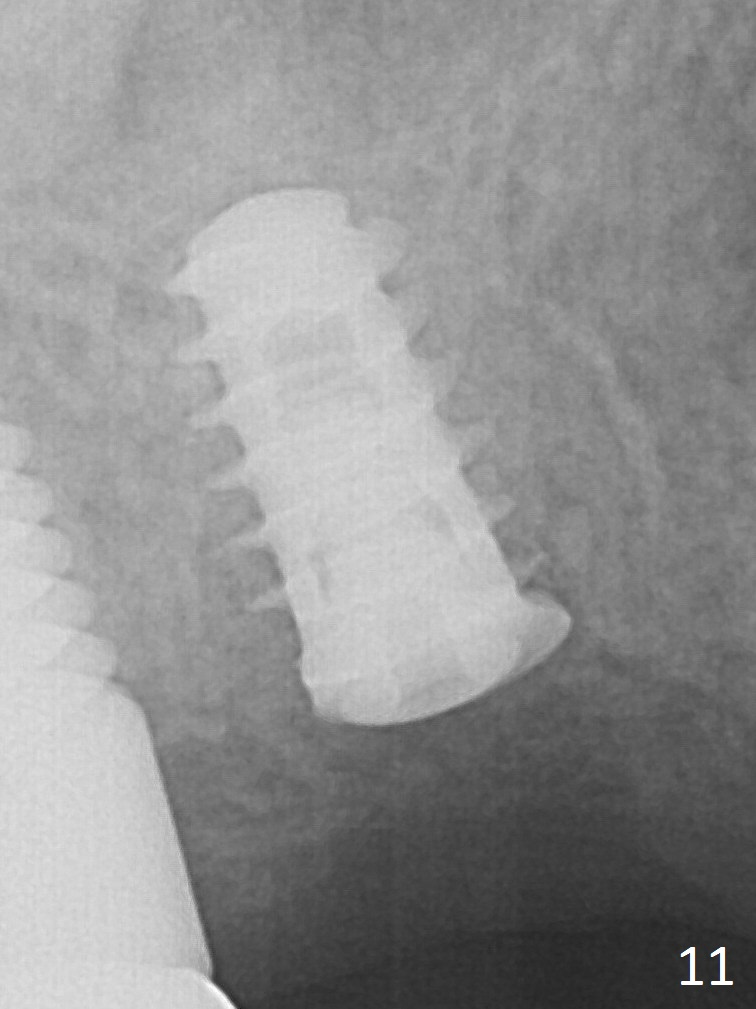

The implant appears to be osteointegrating 3.5 months postop (Fig.11).